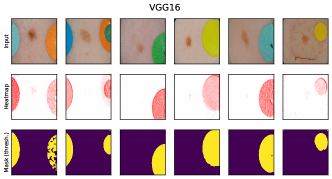

where denotes element-wise multiplication. This yields a heatmap that can be used as a soft mask or converted to a binary segmentation mask, for instance using thresholding techniques like Otsu’s method [57]. An example is shown in Fig. 2 (right), showing soft masks as heatmaps from concept-conditioned local attribution scores, along with binary masks for three known data artifacts: rulers and band-aids for skin cancer detection, and pacemakers in chest radiographs.

6.4 Spatial Bias Localization

To spatially localize biases in input space with CAVs, we compute local explanations for the element-wise product of latent activations and concept direction (see Eq. 2). We use the controlled artifacts, specifically timestamp (HyperKvasir) and micropscope (ISIC2019) with ground truth concept localization masks for evaluation. We compute (1) the percentage of relevance within the ground truth mask and (2) the Jaccard index, or Intersection over Union (IoU), of the binarized localization mask with the ground truth. In Fig. 9, we report both metrics using CAVs computed on different layers of VGG16 and ResNet50. The layer choice for concept representations is key, as for example middle layers perform better to localize timestamps and earlier layers are more effective to localize the microscope. In comparison with Fig.7, we find that the optimal layer for bias localization may differ from the one for sample retrieval. Interestingly, the IoU for the microscope artifact is consistently low, as models primarily focus on the border of the circle instead of the entire area, as indicated by qualitative results in Appendix A.6.3. Unlike artifact relevance, the IoU metric also measures how much of the expected areas the computed mask does not cover.